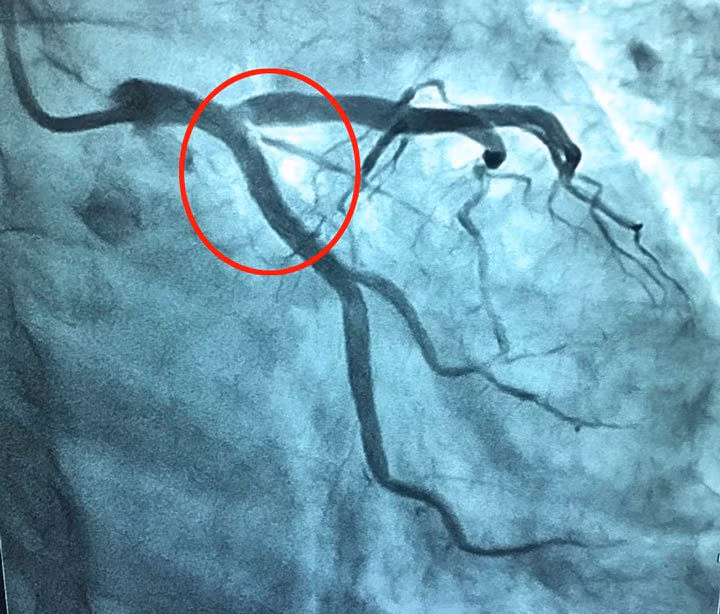

Hình ảnh tắc mạch của người bệnh sau can thiệp (vùng khoanh tròn màu đỏ)

Người bệnh được chẩn đoán: Nhồi máu cơ tim cấp/đa hồng cầu, được nhanh chóng chuyển phòng can thiệp tim mạch chụp mạch vành, kết quả huyết khối trên nền mảng xơ vữa gây bán tắc động mạch mũ, đã được can thiệp hút huyết khối và đặt stent.